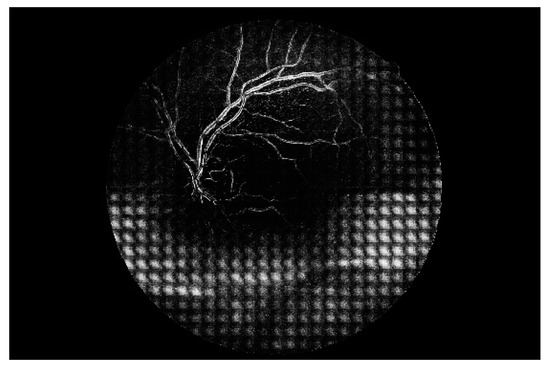

Figure 7 shows a simple example of the MLP method used in this study. The high-resolution fundus (HRF) [74] image dataset contains higher-quality retinal images compared to those of DRIVE, and provides both low- and high-quality retinal images. Figure 8 shows a low-quality retinal image. The bottom part of the image is unclear owing to white noise caused by environmental factors. Figure 9 shows a retinal vessel image created by performing vessel segmentation on Figure 8. The white noise seen in Figure 8 also affects vessel segmentation. Figure 10 is a high-quality retinal image and the white noise observed in Figure 8 has disappeared. The bottom part of the vessel stem is clearly visible, which did not appear in the original image. Figure 11 shows a retinal vessel image created by performing vessel segmentation on Figure 10. Unlike Figure 9, the bottom part of the vessel stem is shown clearly.

Figure 10. Retinal image (high quality).

Electronics 09 00767 g010

Figure 11. Retinal vessel image of Figure 10.

Electronics 09 00767 g011